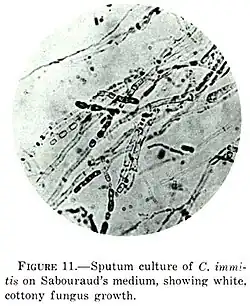

C. immitis can cause a disease called coccidioidomycosis (valley fever).[8][9][10] Its incubation period varies from 7 to 21 days.[11] Coccidioidomycosis is not easily diagnosed on the basis of vital signs and symptoms, which are usually vague and nonspecific. Even a chest X-ray or CT scan cannot reliably distinguish it from other lung diseases, including lung cancer. Blood or urine tests are administered, which aim to discover Coccidioides antigens. However, because the Coccidioides creates a mass that can mimic a lung tumor, the correct diagnosis may require a tissue sample (biopsy). A Gomori methenamine silver stain can then confirm the presence of the Coccidioides organism's characteristic spherules within the tissue. The C. immitis fungus can be cultured from a patient sample, but the culture can take weeks to grow and requires special precautions on a part of the laboratory staff while handling it (screw cap vials and sterile transfer hoods are recommended).[12] It is reported as the tenth-most often acquired infection in the laboratory conditions with two documented deaths.[2] Until October 2012, C. immitis had been listed as a select agent by both the U.S. Department of Health and Human Services and the U.S. Department of Agriculture, and was considered a biosafety level 3 pathogen.